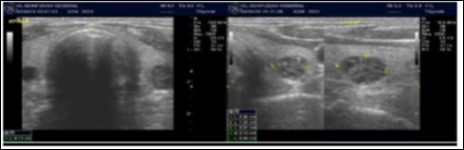

The reported prevalence of nodular thyroid disease depends on the population studied and the methods used to detect nodules 16. Our study population is unique as it is composed entirely of ESKD patients. We also used ultrasound as a method of detecting thyroid abnormalities. In our study the prevalence of thyroid nodular pathology as detected by ultrasound was found to be 57.6% mirror image what reported in the literature as it has been reported that nodules found on ultrasonography suggest a prevalence of 19 to 67%17, 18; and in other publications it has been reported to range from 50% to 70% 7, 8. Figure 3A below shows an Ultrasound detected thyroid nodule.

The prevalence of thyroid nodule is also influenced by age. In one study, 30 % of subjects 19 to 50 years of age had an incidental nodule on ultrasonography19. However, from our work we found that the presence of nodules increases with age. This may explain the reported low incidence of thyroid nodule in the age group 19-50 years. Also, with the widespread use of sensitive imaging in clinical practice, incidental thyroid nodules are being discovered with increasing frequency.

High-resolution ultrasonography (USG) is the most accurate and cost-effective method for evaluating and observing thyroid nodules 3. Although there is some overlap between ultrasound appearance of benign and malignant nodules, certain USG features are helpful in differentiating the two. Iso-or hyper-echogenicity of the thyroid nodule in conjunction with a spongiform appearance is the most reliable criterion for benignity of the nodule on gray-scale ultrasound, Figure 4A. Other features like nodule size <1 cm, width > length, presence of hypoechoic or hyperoechoic halo around the nodule, Figure 4A and Figure 4B, caused by fibrous capsule compressing thyroid tissue, and coarse/curvilinear calcification are less specific but may be useful ancillary signs4 ,6. "Ring down" or "comet-tail" artifact or sign is typical of benign cystic colloid nodule, Figure 520. Perinodular flow or spoke-and-wheel-like appearance of vessels on color Doppler examination is characteristic of a benign thyroid nodule. However, this flow pattern may also be seen in thyroid malignancy. A complete avascular nodule is very unlikely to be malignant 4.